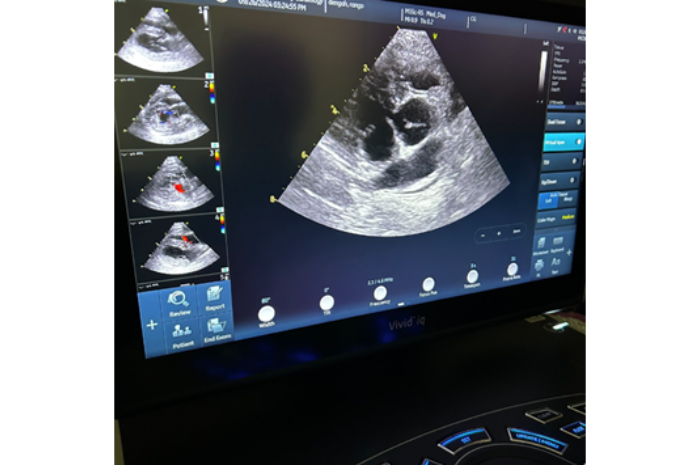

Echocardiogram (heart ultrasound) looks at the size of the chambers of the heart and measure if it is strong enough to handle general anesthesia.

An echocardiogram allows the cardiologist to measure chambers of the heart and quantify its function.